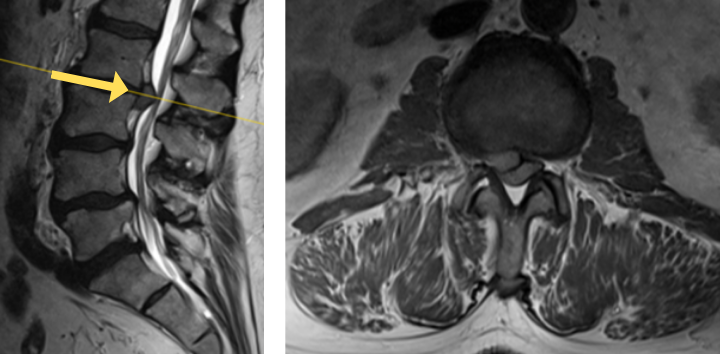

Image 3. Post-op x-rays that show L4/L5 transforaminal lumbar interbody fusion (TLIF). There was also removal the L2/L3 disc herniation but no need for instrumentation.

Dr. Imani was able to decompress both the L2/L3 level (with disc herniation removal) and the L4/L5 level. Additionally, L4/L5 level was fused using titanium screw and an expandable interbody cage. This was performed with a very small incision. The patient has no more leg pain and back pain, and is doing very well!